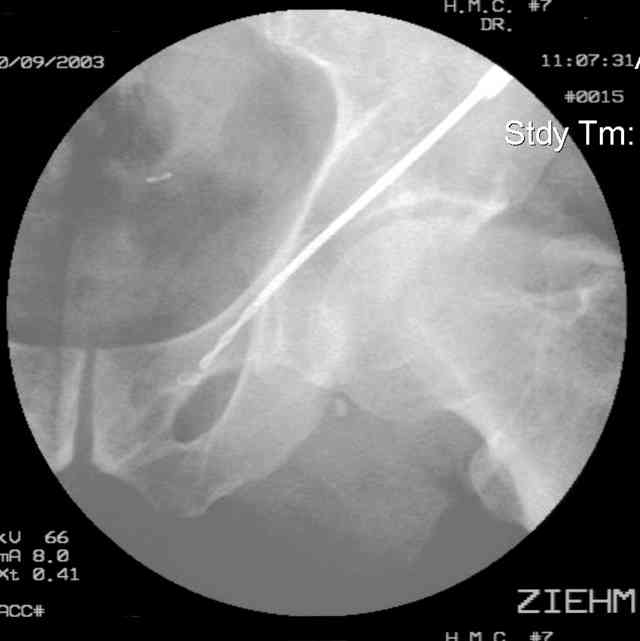

Prone Inlet

OK, now we're inserting the drill percutaneosuy using a sleeve. This fluoro shot is not for this patient (notice no clamp) but I was too lazy to go searching the PACS for one with the clamp on, so pretend...I'll save the next ones and send along...the imaging is the same and the clamp doesn't obstruct imaging other than very rarely...you can always tilt the C-arm a bit to clear it if the clamp obstructs the exact spot that you'd like to see. We'll assume that everyone knows the safe zone for a medullary ramus screw. Use a calibrated drill and sleeve of known length to simplify your life...or use Alex's fancy cannulated screws...I like 3.5mm screws because the oscillating 2.5mm drill bounces and remains intraosseus when it oscillates and contacts endosteal cortical ramus... so will the screw, and like a long bent screw IF the fracture is clamped... if unclamped, when the screw contacts the endosteum, it pushes the reduction apart instead of bouncing. The big 7mm cannulated screws fit few patients and extrude...we very rarely use them any more...you'll see an old one later.

Prone Obturator-Outlet

Screw insertion using the obturator-outlet combination image.